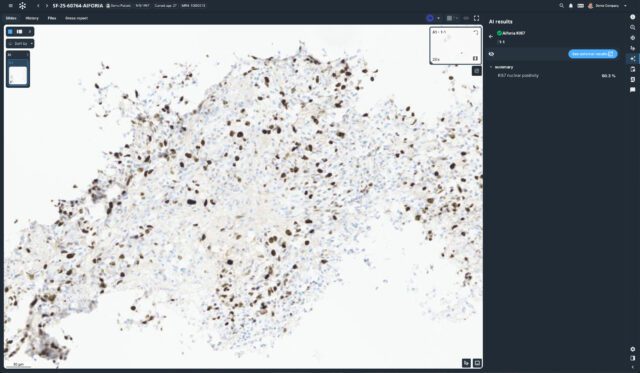

Built with pathologists to deliver an ultrafast cloud-based viewer, flexible worklist, integrated workflows, and state-of-the-art AI.

Techcyte Fusion: The unified anatomic and clinical pathology AI platform

What to expect from the Techcyte platform